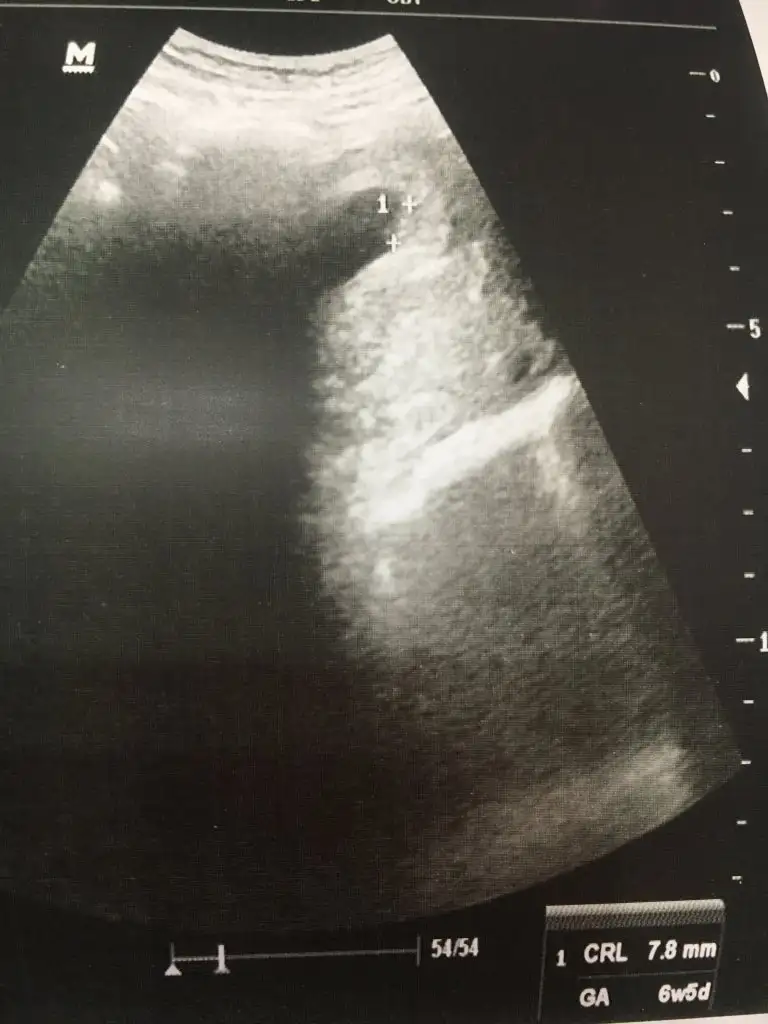

Ultrason fotoğrafın var mii bebisin boyu kaç çıktı bu aradabenim mercimek bu

Maşallah senin mercimek epey net çıkmış, benim doktor uzaktan çekmiş çok. Benimki 7,8 mm. Bak benim mercimek de bu. Kankalar tanışsın :))

Ben bu mercimeği yerim ya uzak ama yine de belli oluyor şuna bak

Benimkini doktor yaklastirdi boyunu falan ölçerken bende videoya aldım ordan bu görüntü kağıtta da aynı bu şekilde oturuyor gibi

Benimkisi normalde 7+2 günlüktü ultrasonda da 7+1 çıktı boyuda 10 mm dedi aynı gidiyor bizim kankiler

Seninki çok artistik poz vermiş yalnız maşallah :)) Bebnim hiç aklıma gelmedi bak ekrandan çekmek insan heyecandan naptığını bile bilmiyor ki. Ben bir sonraki muayeneyi bile sormayı unutmuşum. Tekrar geri dönüp sordum :))

Ultrason kağıdında da aynı ama orda soluk çıkmış biraz. Oturuyor gibi pozu var tam artist